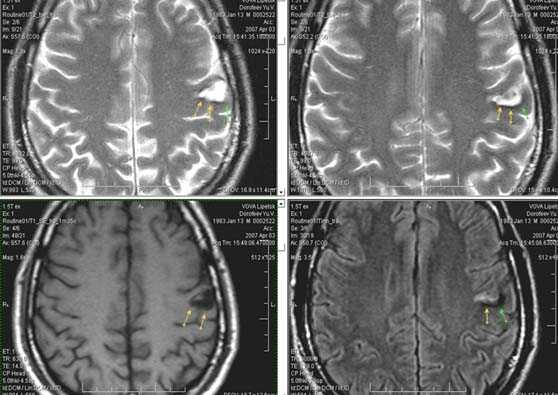

Лакунарное ишемическое ОНМК на фоне хронической сосудистой недостаточности.

Некоторые инфаркты при дисциркуляторной энцефалопатии протекают бессимптомно. Это «немые» инфаркты, которые, как правило, локализуются в глубоких отделах мозга и диагностируются только при МРТ. Этот случай показывает возможности выявление очага ограниченного ишемического ОНМК базальных ядер слева на фоне хронической ишемии.

Выраженная сосудистая энцефалопатия с наличием множественных очагов хронической ишемии, лакунарных постишемических кист. Программа ДВИ четко показывает фокус острого ОНМК в базальных ядрах справа на фоне лейкодистрофии.